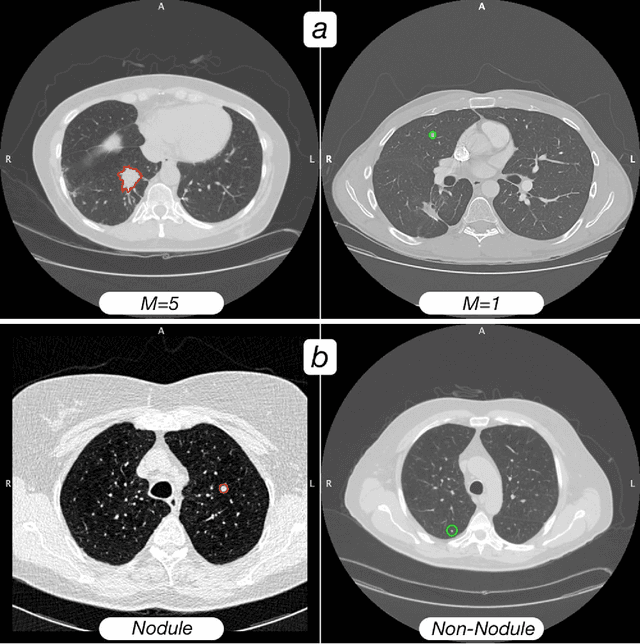

Abstract:Computed tomography (CT) examinations are commonly used to predict lung nodule malignancy in patients, which are shown to improve noninvasive early diagnosis of lung cancer. It remains challenging for computational approaches to achieve performance comparable to experienced radiologists. Here we present NoduleX, a systematic approach to predict lung nodule malignancy from CT data, based on deep learning convolutional neural networks (CNN). For training and validation, we analyze >1000 lung nodules in images from the LIDC/IDRI cohort. All nodules were identified and classified by four experienced thoracic radiologists who participated in the LIDC project. NoduleX achieves high accuracy for nodule malignancy classification, with an AUC of ~0.99. This is commensurate with the analysis of the dataset by experienced radiologists. Our approach, NoduleX, provides an effective framework for highly accurate nodule malignancy prediction with the model trained on a large patient population. Our results are replicable with software available at http://bioinformatics.astate.edu/NoduleX.